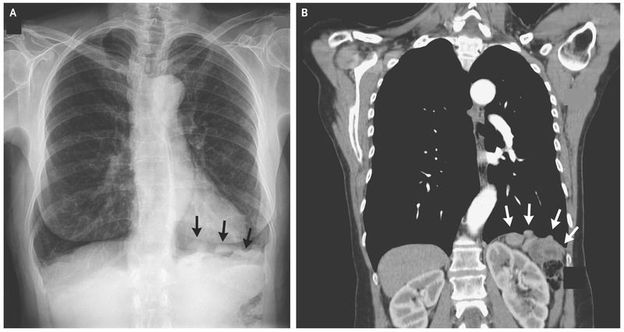

A 62-year-old woman with progressive shortness of breath and a 40-pack-year smoking history was referred for pulmonary evaluation after a radiograph of the chest showed nodularity along the left hemidiaphragm (Panel A, arrows), raising the possibility of cancer. The radiograph was otherwise unremarkable except for hyperinflation suggestive of emphysema and mild thoracic scoliosis. Her medical history was notable for a gunshot wound to the thoracoabdominal region 28 years earlier, which had resulted in injury to the liver, left hemidiaphragm, and spleen, requiring a laparotomy and splenectomy. Computed tomography revealed several small, basilar, pleural nodules on the left side (Panel B, arrows) as well as a diaphragmatic defect and nodules in the splenic bed, with findings of prior splenectomy. A technetium-99m–labeled scan with heat-damaged red cells confirmed the diagnosis of splenosis. This study showed remnants of splenic tissue above and below the left hemidiaphragm, including nodules in the left hemithorax that extended as high as the aortic arch. Splenosis refers to heterotopic viable splenic tissue that is implanted because of spillage or intravascular migration of cells from splenic pulp. This condition usually follows splenic trauma with rupture, accidental damage to the spleen during surgery, or elective splenectomy. The degree of immunocompetence was uncertain, and we recommended that the patient be immunized against encapsulated bacteria. She began using an inhaler for chronic obstructive pulmonary disease, which was confirmed with the use of spirometry and explained her initial symptoms of progressive shortness of breath, and had a good response.